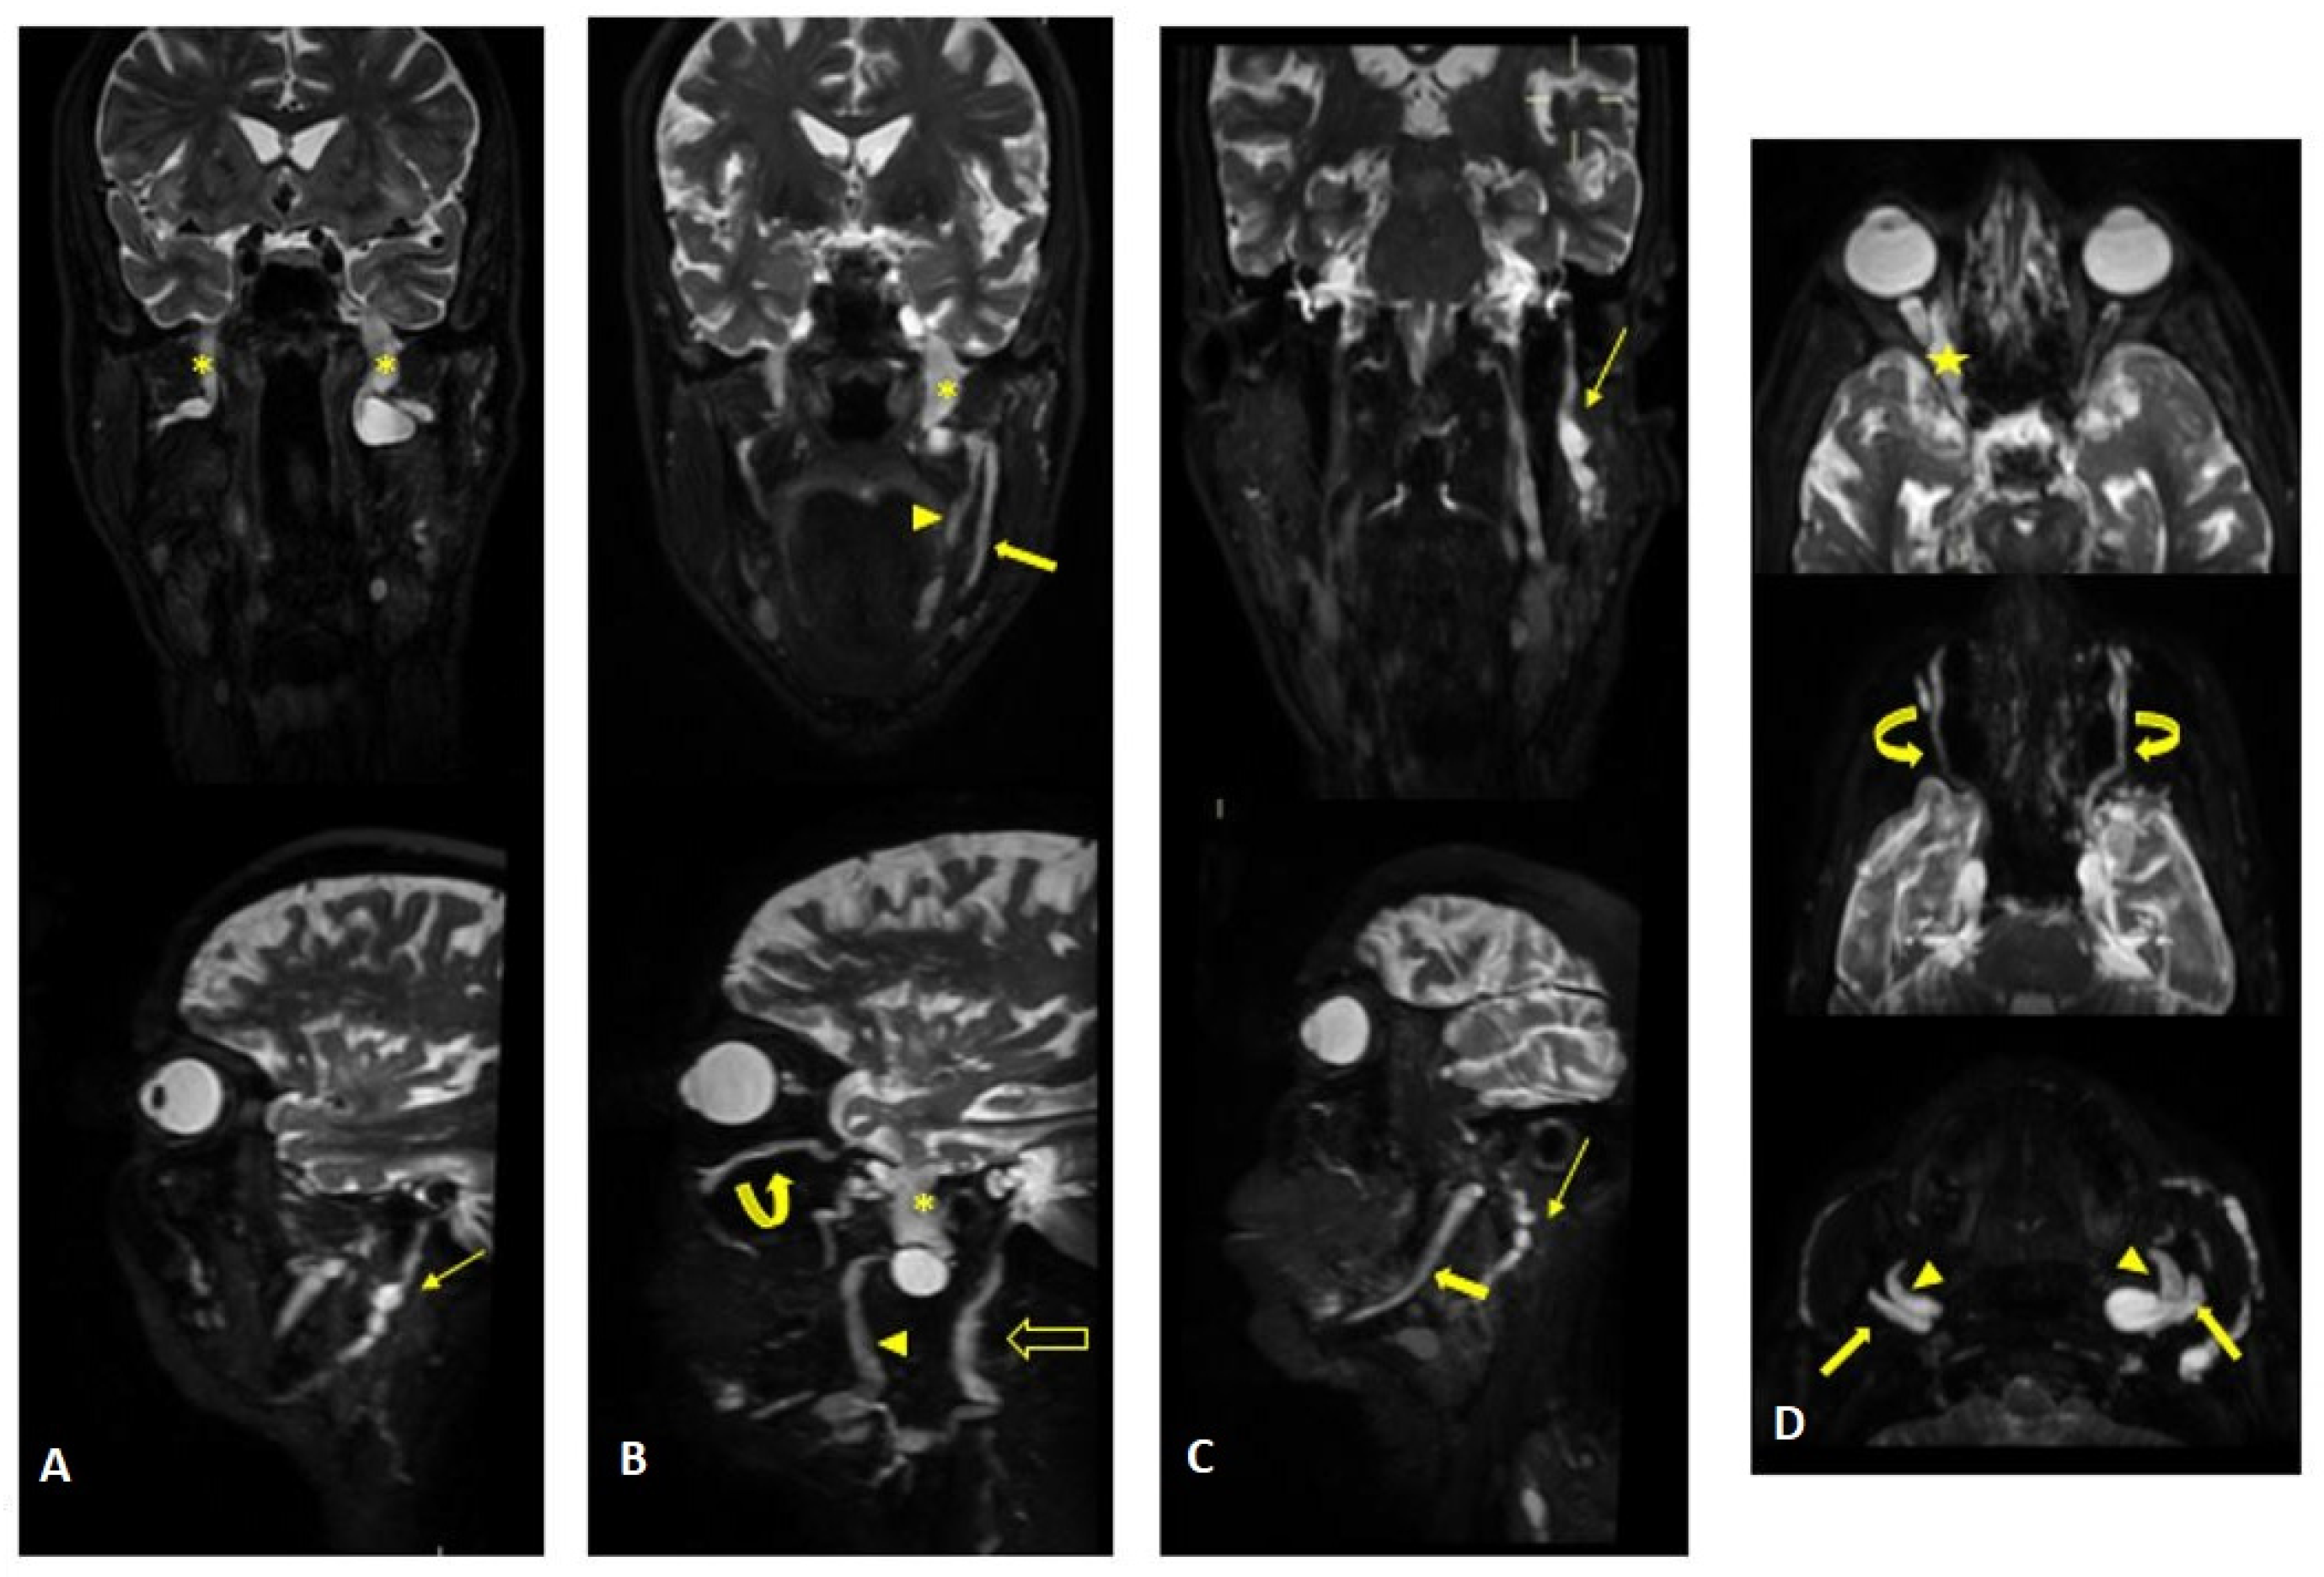

Figure 2.

MR (multiplanar reconstructions) of 3D cube neurography images show pathological, thickened cranial nerves along their extracranial course, with some cystic-like components. The images show the involvement of trigeminal branches V1 in ((D)—yellow star), V2 in ((B,D)—curved arrows with a transverse diameter after inferior orbital foramen: left 1.8 mm; right 2.6 mm) and V3 from its passage in the foramen ovale (asterisks in (A,B)) to its lingual (arrowheads in (B,D)) and alveolar divisions (thick arrows in (B–D)); the involvement of the left facial nerve in its intraparotid course (thin arrows in (A,C)) and the hypoglossal nerve (open arrow in (B), transverse diameter at C1 level: left 4.6 mm; right 2.1 mm).